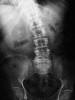

Osteoporosis. Cifosis.